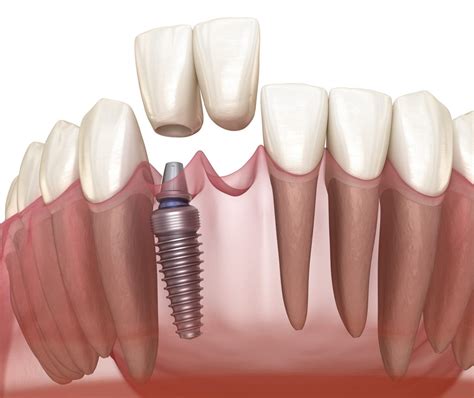

Losing a tooth in your smile line can be a deeply unsettling experience, impacting not only your ability to chew and speak clearly but also your self-confidence. When faced with this issue, many patients turn to front dental implants as the premier solution for restoring both form and function. Unlike traditional bridges or dentures, which sit on top of the gums, dental implants serve as a permanent replacement for the entire tooth structure, from the root to the crown. By mimicking the natural tooth’s anatomy, these implants offer unparalleled stability and a remarkably lifelike aesthetic that is essential for front-facing teeth.

Implant Placement Surgical insertion of the titanium post into the jawbone.

Osseointegration A healing period of 3–6 months where the bone fuses to the implant.

Abutment & Crown Attaching the connector and the final, custom-made ceramic crown.